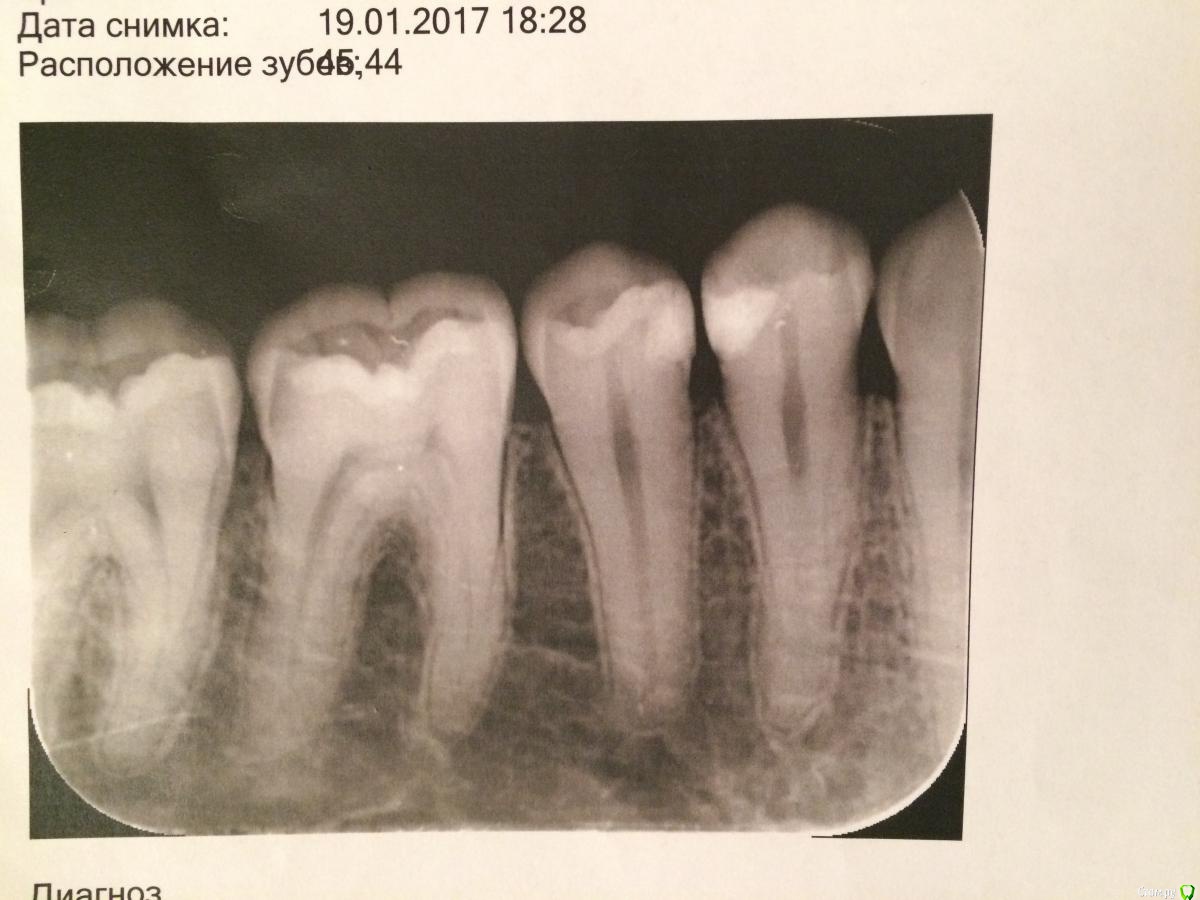

andrey12345678912345 Опубликовано 27 января, 2017 Поделиться Опубликовано 27 января, 2017 Привет! Полгода назад лечил зубы 44, 45. Поставили пломбу (снимок прилагается). Две недели назад заболела челюсть справа, внизу, в основании зубов 44, 45, где-то внутри, между зубами, конкретнее сказать не могу где болит. Вечерами боль усиливается. Пару раз просыпался от боли, пил обезболивающее один раз. При надавливании на зубы боли нет. Если стучать по зубам тоже боли нет. На холодное и горячее реагируют также как и остальные зубы. 44, 45 зубы выглядят здоровыми, цвет не изменён. Ну, то есть зубы не болят, где-то внутри челюсти болит. Сейчас болит меньше, иногда по утрам, вечером не болит. Вчера вообще боли не было весь день. Пошёл к стоматологу, сделали снимок, врач сказала надо лечить канал. Посчитала стоимость лечения - 6100 рублей. Больше ничего не сказала, диагноз не указала. Друзья, нужна ваша консультация. Какой диагноз? Нужно ли лечить канал? В ближайшее время или подождать какое-то время? Соответствует ли заявленная стоимость лечения рынку? Ссылка на комментарий

St. Опубликовано 28 января, 2017 Поделиться Опубликовано 28 января, 2017 Возможно воспалился нерв в одном из зубов. В 44 пломба находится достаточно близко к нерву.Если болит, и тем боле не дает спать, то конечно тянуть с лечением не стоит. Но если Вы сомневаетесь сходите еще куда-нибудь на консультацию. Ссылка на комментарий

andrey12345678912345 Опубликовано 30 января, 2017 Автор Поделиться Опубликовано 30 января, 2017 Возможно воспалился нерв в одном из зубов. В 44 пломба находится достаточно близко к нерву.Странно, пломбу заметили, а пятно у корня зуба нет. Если болит, и тем боле не дает спать, то конечно тянуть с лечением не стоит. Но если Вы сомневаетесь сходите еще куда-нибудь на консультацию. Вот я и пришёл сюда на консультацию. Ссылка на комментарий

red_butler Опубликовано 30 января, 2017 Поделиться Опубликовано 30 января, 2017 Речь идет о очной консультации у другого врача. По одному снимку диагноз не поставить. Ясно только одно, что лечить зубы, 4 и 5 нужно. И тот что беспокоит, как можно скорее. Пятно на снимке, это ментальное отверстие. Да, и финансовые вопросы на форуме не обсуждаются. 1 Ссылка на комментарий